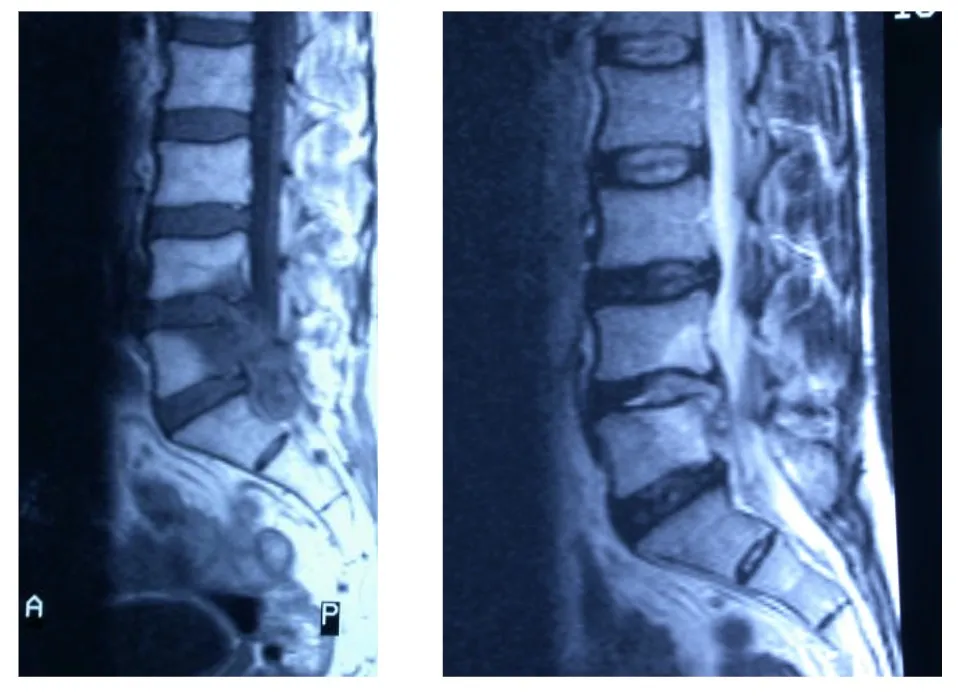

Resonancia magnética (RM)

Constituye la prueba de imagen de elección para el diagnóstico y seguimiento de la espondilodiscitis. La RM presenta una sensibilidad y especificidad superior al 90%, permitiendo una visualización óptima del disco, los cuerpos vertebrales, los abscesos epidurales y la afectación de partes blandas paravertebrales.

La clasificación de la espondilodiscitis por resonancia magnética distingue diferentes estadios según los hallazgos radiológicos:

| Estadio | Hallazgos |

|---|---|

| Estadio I | Hematoma y radiolucidez localizada en los platillos de la vértebra |

| Estadio II | Edema vertebral y/o sospecha de acumulación de líquido dentro del cuerpo vertebral con mala demarcación de la lesión |

| Estadio III | Intensidad de señal irregularmente aumentada en la resonancia con confinamiento dentro del ligamento longitudinal posterior |

| Estadio IV | Acumulación evidente de líquido en el disco asociado a destrucción de los platillos y extensión a lesiones epidurales |

| Estadio V | Desaparición del disco con colapso vertebral y afectación del cuerpo vertebral y arco posterior así como de los ligamentos y músculos paravertebrales |